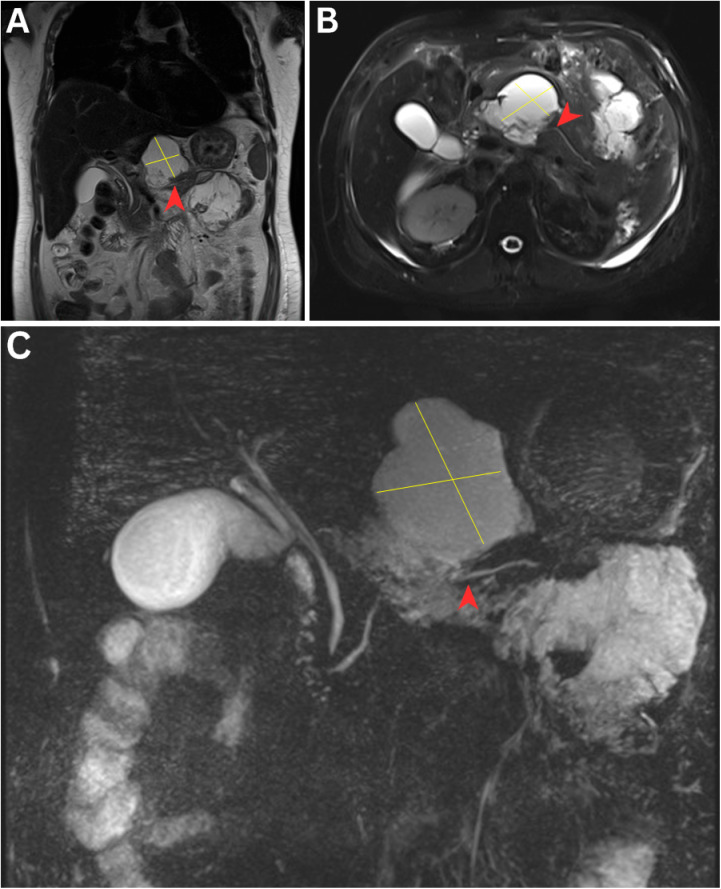

Disconnected Pancreatic Duct Syndrome in Complicated Necrotising Pancreatitis.